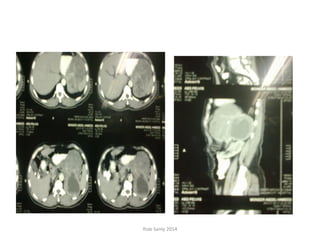

• CT Abdomen and pelvis (13-11-2011): Large

oblong retroperitoneal cystic collection at left

iliac region extending to left lumbar region

measuring 22 X 5 X4 cm. Extending sup. To

reach lower pole of spleen, displacing lt.

kidney medially + multiple enlarged inguino-

iliac LNs 1-3.5 cm. in diameter.

• Follow- up CT Abdomen and pelvis (07-12-

2011): Progressive course since the last study

regarding the left ilio-lumbar cystic mass and

stationary course of lymphadenopathy.

• CT guided aspiration cytology of 5 cc. of

turbid hemorrhagic fluid on (13-12-2011):

Exudative reaction.

(No Atypia or Malignancy)